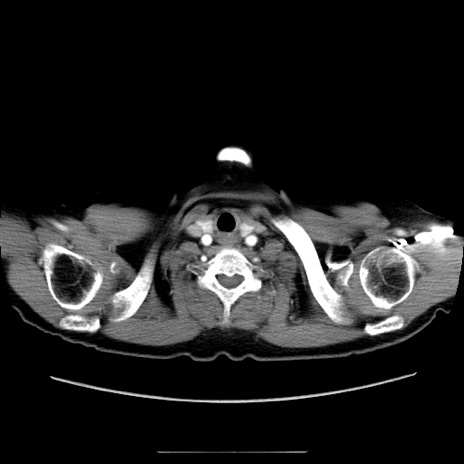

冠状断像

【症例】70歳代女性

【主訴】お腹が張る

【現病歴】1週間くらい前から腹部膨満の自覚あり。昨日夜から増悪したため、本日救急外来受診。

【身体所見】意識清明、BT 36.5℃、BP 165/106mmHg、HR 80bpm、SpO2 98%、腹部:膨満、軟、自発痛・圧痛なし、触診にて不快感あり、腸蠕動音:減弱

【データ】WBC 12600、CRP 1.04